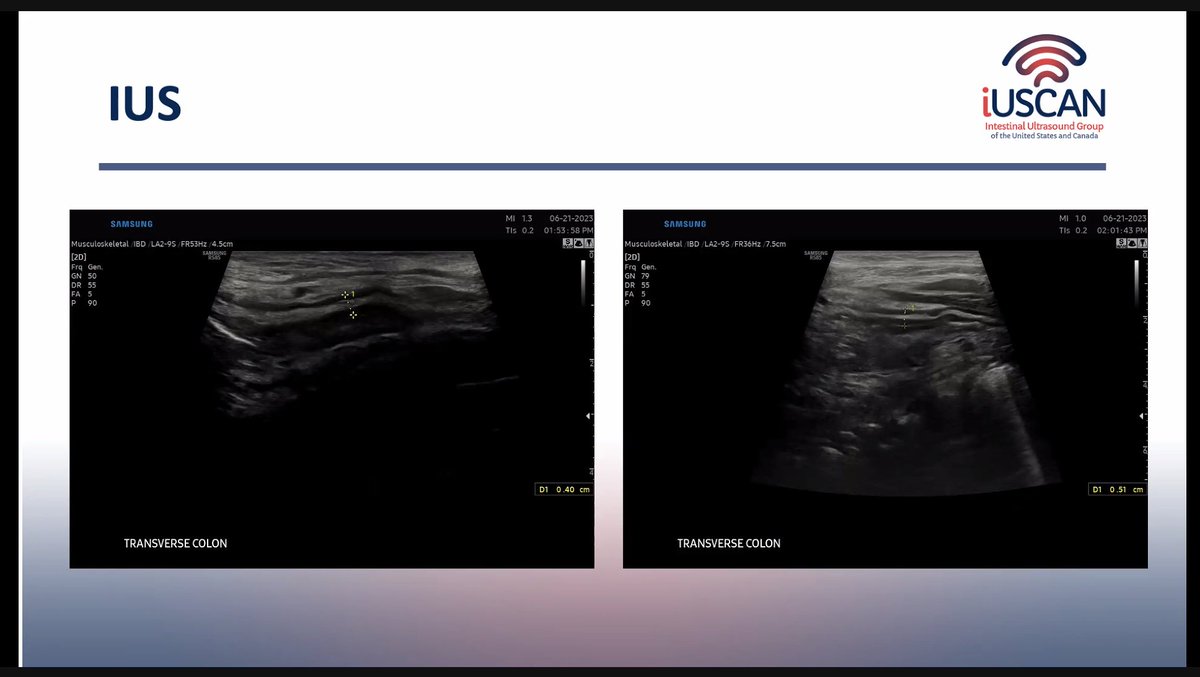

Excited to demonstrate how intestinal ultrasound is revolutionizing IBD care for patients in the USA at #AIBD2023! if you wanted a hands-on, personal experience to see how to bring IUS yo your pts, come learn with @KrugCleveland and myself throughout the conference.

Fantastic cases yesterday from @yusukemiya73 on how #IUS identified the need for dilation in a patient with obstruction and @drhughiefraser who showed that IUS predicts risk of flare despite improved symptoms (and can be helpful in non-compliant patients!)

IUSMonthly continues through the summer months! Thanks to @MaiaKayalMD & @KrugCleveland for presenting on the use of #IUS in pregnant #IBD patients and @DrMikeDolinger for updating us on his previous pediatric #ASUC case. See you next on August 8th!